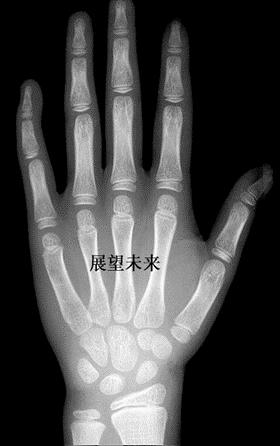

骨龄,按字面理解也就是骨骼的年龄,称为生物年龄,是通过骨骼的发育程度,来测定年龄的一种方法。测骨龄也不是很神秘或什么“黑科技”,它的操作方法其实很简单:通常家长只要带孩子去照个左手(包括掌指腕关节)的正面X光片,然后交给医生做评估就可以了。

一般医生会拿标准图谱与孩子的X光片进行比对,比较接近哪个年龄阶段,就认为骨龄在几岁。

为了确保检测的准确性,一些专业机构也会引进人工智能来协助测骨龄,目的是减少医生主观判断因素的干扰。

拍骨龄X光片的辐射量是很小的,相当于我们坐了2分钟飞机所受到的辐射量,可以忽略不计,所以家长不用因为这个问题担心。